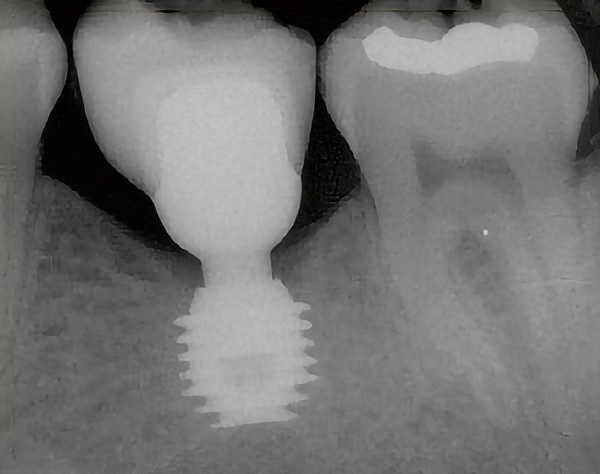

Implantacja systemem Bicon

Implantacja systemem Bicon to nowoczesna metoda uzupełniania braków zębowych z wykorzystaniem krótkich implantów o unikalnej konstrukcji i bezśrubowym połączeniu stożkowym. System ten znany jest z wysokiej stabilności, szczelności oraz bardzo dobrych efektów estetycznych.

Zabieg polega na wszczepieniu implantu do kości w miejscu utraconego zęba. Implant Bicon charakteryzuje się:

• plateau (talerzykową) budową sprzyjającą integracji z kością,

• krótszą długością – co często pozwala uniknąć rozległych zabiegów augmentacji kości,

• bez śrubowym, bakteriostatycznym połączeniem stożkowym (locking taper),

• możliwością osadzania korony cementowanej bez klasycznej śruby protetycznej.